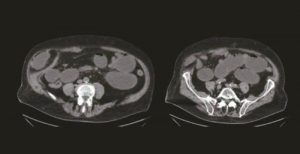

Du diagnostic de gastroentérite à une prise en charge au bloc opératoire ! Importance de la répétition des examens cliniques en médecine gériatrique

La médecine gériatrique repose avant tout sur une évaluation clinique des patients pris en charge. Cependant, dans certains cas et face au caractère peu spécifique de certains symptômes, le recours…